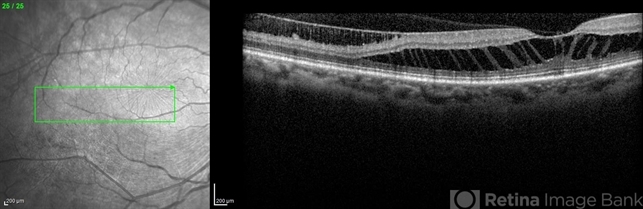

- Infrared and HD-OCT of the right eye in a 55-year-old African American female with high myopia (more than -6.00 D), BCVA: 20/25 OU Cartwheel appearance of the fovea in the infrared imaging is visible. HD- OCT demonstartes schisis in different layers of the retina (both NFL and OPL; notice stretching of the Muller cells); VMT is also present . Outer retinal layers are preserved which explains the good vision . She had the same findings in OS.